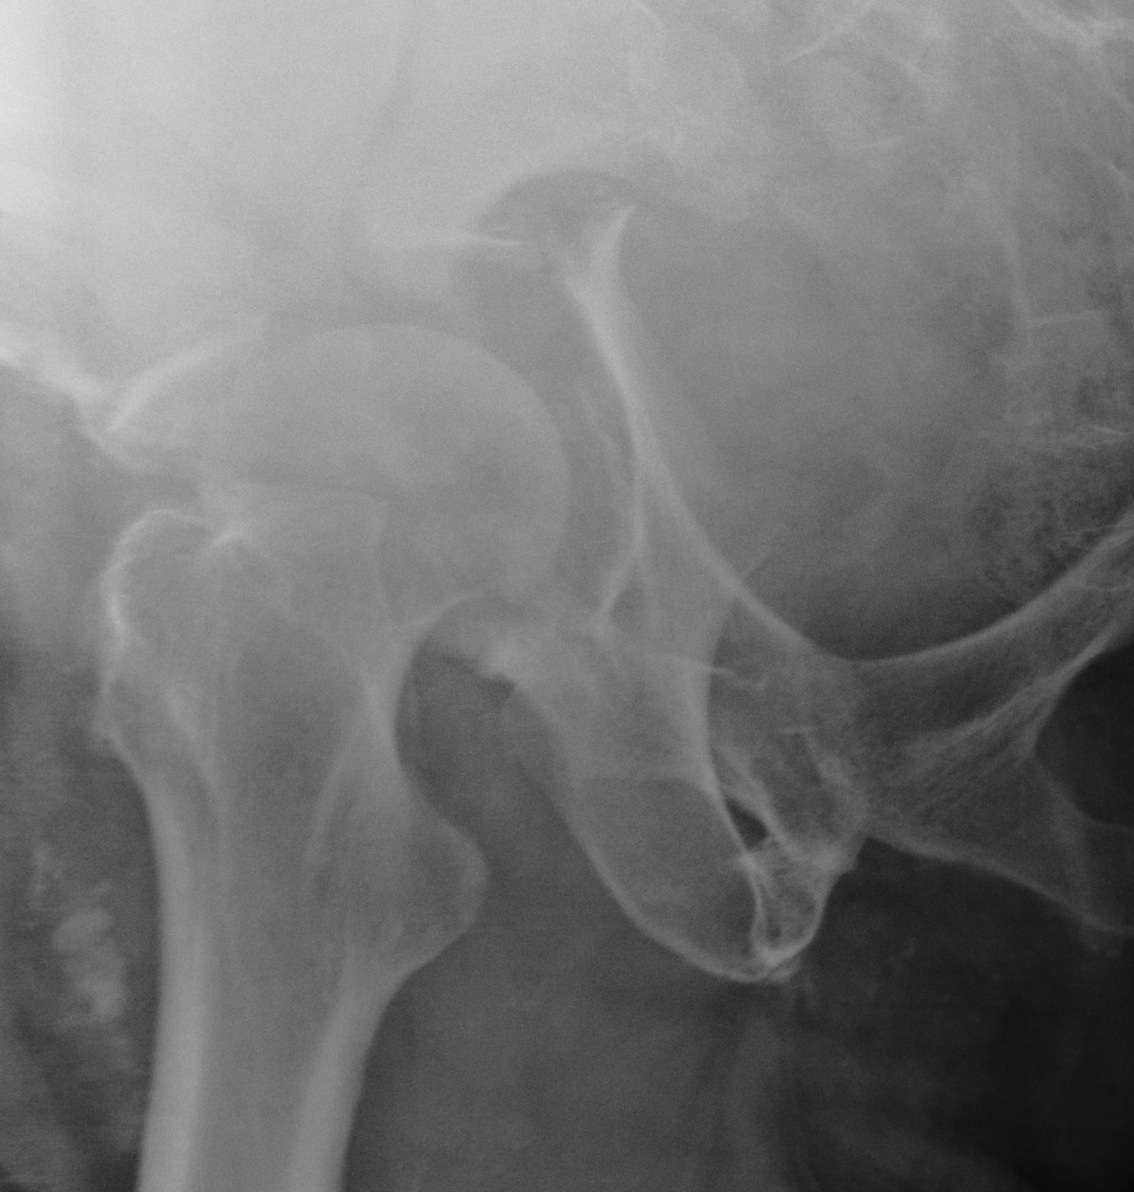

Judet views / 45o obliques

Internal Oblique / Obturator Oblique

- affected side rotated forward

- anterior column + posterior wall

External Oblique / Iliac Oblique

- unaffected side rotated forward

- posterior column + anterior wall